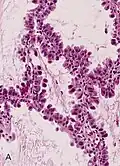

Mucinous BAC

Non-mucinous BAC